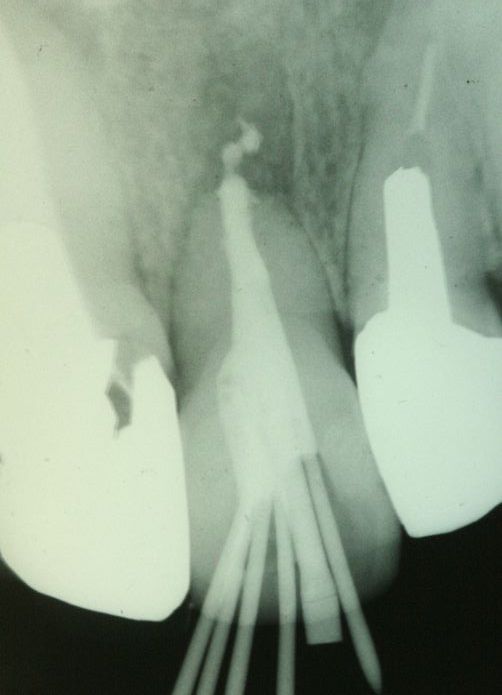

今日患者さんの了解が取れたのでレントゲン画像をUPしておきます。

歯の全長は実測17mmです、レントゲンから骨内にある歯根長を推測すると約5mm弱くらいだと思います。

問題なく何でも咬めるそうです。

参考になさってください。

画像1 治療前(向かって右の歯)

画像2 根管充填後